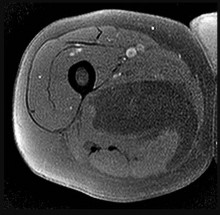

Figures 7a through 7d are the radiograph, MR images, and biopsy specimen of a 35-year-old man who has a painful, slowly enlarging knee mass. Which chromosomal translocation is characteristic of this pathology?

Synovial sarcoma is a soft-tissue sarcoma that usually occurs in young adults. Synovial sarcoma often causes pain, unlike most soft-tissue sarcomas, which generally do not cause pain. Imaging characteristics include soft-tissue calcifications on plain radiographs and a heterogeneous mass that is generally isointense to muscle on T1-weighted images and hyperintense to muscle on T2-weighted images. There are biphasic and monophasic types of synovial sarcoma. The biphasic

type, which is depicted here, has both spindle cell and epithelial components and will stain for both vimentin and cytokeratin. More than 90% of patients with synovial sarcoma have a characteristic genetic translocation of t(X;18), which results in the fusion protein SS18-SSX. This translocation can be stained for use of florescence in situ hybridization technology. t(11;12) is seen in Ewing sarcoma. T(9;22) is seen in extraskeletal myxoid chondrosarcoma. t(12;16) is seen in myxoid liposarcoma.